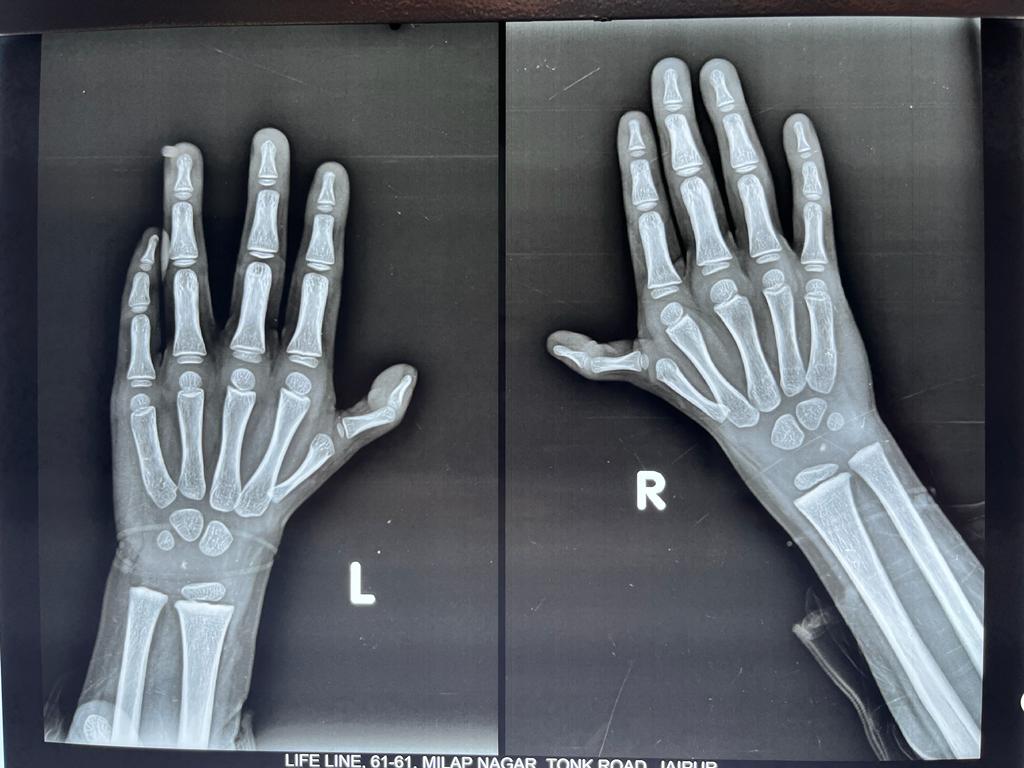

Fracture Scaphoid Treated With Bone Graft And k Wire Fixation

Translocation of Ulna for GCT Of Distal Radius

Pre and post of pics of 3 months old fracture 4 th metacarpal with pain shortening of finger and loss of knuckle prominence